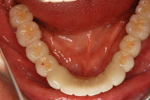

③ 下の顎・セラミッククラウン、ブリッジセット状態

④ 治療後。前から見た状態